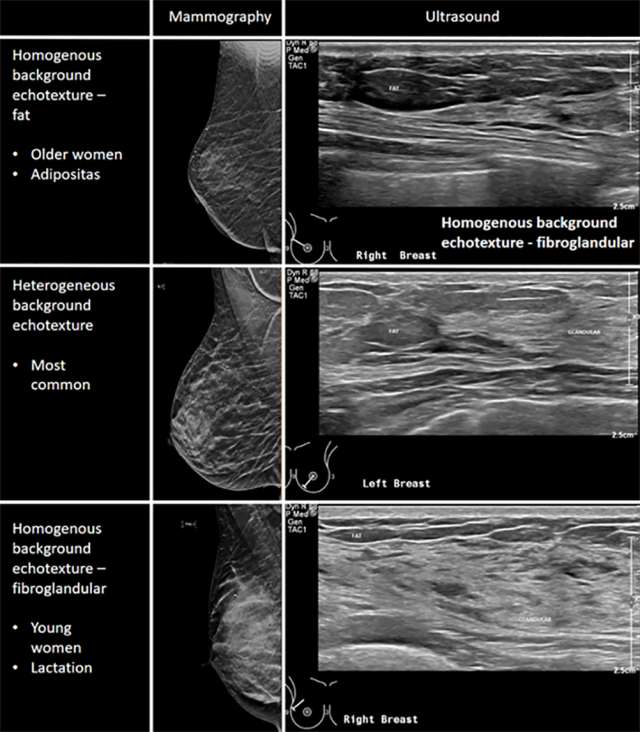

Basics of Breast Ultrasound Radiology UCLA Health